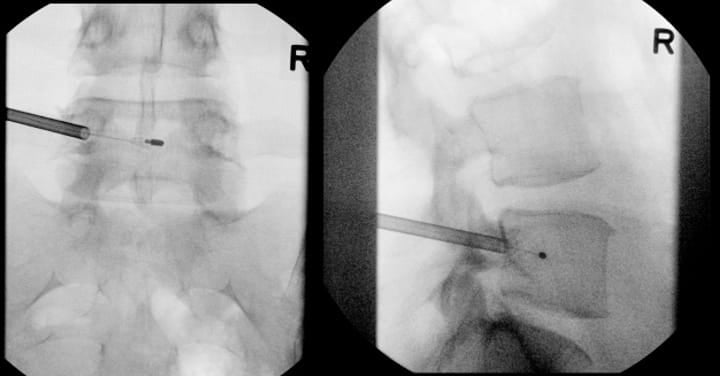

Monitored anesthetic care is the most common type of anesthesia performed, although general anesthesia is an option as well. Local anesthesia is administered, followed by careful trocar advancement under fluoroscopic guidance. It is very important to check AP and lateral images to ensure that the trocar does not violate the medial border of the pedicle on the AP image prior to breaching the posterior wall of the vertebral body on lateral imaging. The trocar passes through the lateral pedicle aspect, staying superior to inferior cortex and lateral to medial cortex. Once the posterior vertebral body cortex is breached, the curved cannula assembly is advanced toward the stem of the basivertebral nerve at a point located 30%-50% of the sagittal diameter of the vertebral body (closer to the posterior wall). This allows for radiofrequency probe positioning proximal to the location of basivertebral nerve arborization. Final probe positioning varies by vertebral level to optimize targeting of the basivertebral nerve terminus. For the L3, L4, and L5 levels, the probe should be positioned at the midpoint between the superior and inferior endplates (approximately 50% of the cephalo-caudal diameter of the vertebral body) and 30-50% of the vertebral body width from the posterior wall (Figure 2). However, S1 vertebral anatomy requires modified positioning due to the unique sacral morphology. At the S1 vertebral body, the probe should be positioned closer to 50% of the sagittal diameter from the posterior wall and approximately 40% of the distance from the superior endplate to the inferior endplate. Proper positioning at each level is confirmed through multiple fluoroscopic views in both AP and lateral projections before initiating the ablation cycle.